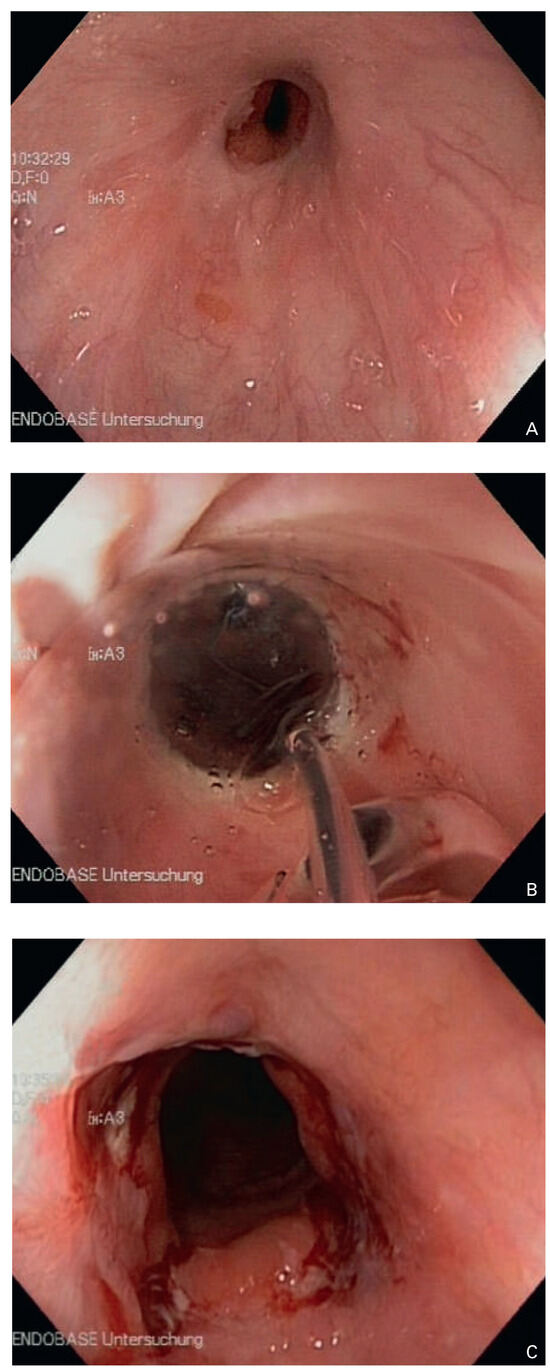

A 41-year-old women with Ebstein’s anomaly required tricuspid valve replacement six years ago. At that time a biological prosthesis was implanted. The tricuspid valve prosthesis became severely stenotic within five years. Instead of re-do surgery, th...